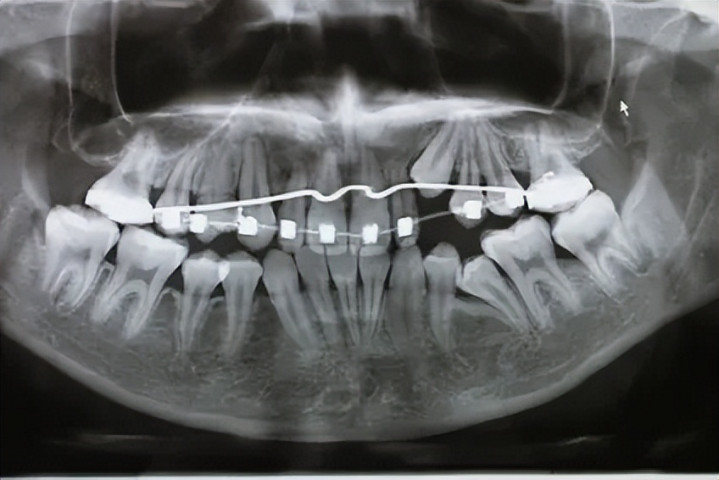

牙齿多、乱,挤占了正常牙的位置,导致咬合芜杂或清洁死角,这种牙留着有害有害。

牙齿太拥堵,需要腾出空间才智排皆。大夫进程精密测量后,为了全体的好意思不雅和咬合功能,拔掉某些功能次要的牙(往往是双尖牙),这叫“计谋性拔牙”。